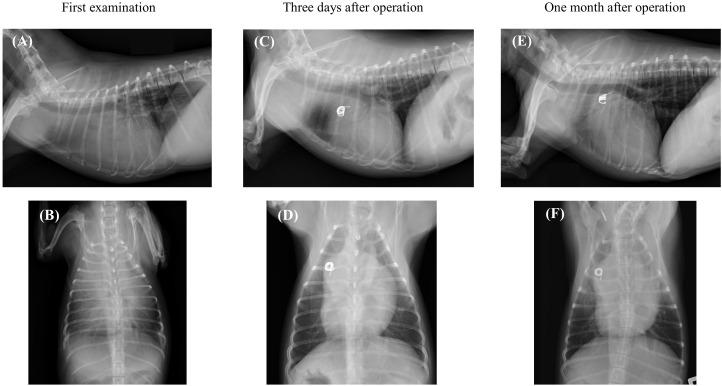

Two dogs with patent ductus arteriosus and severe pulmonary hypertension were presented to our veterinary teaching hospital. In both dogs, sildenafil was initiated to treat pulmonary hypertension, and surgery was supposed to be scheduled after dose titration. Although no obvious improvement in pulmonary hypertension was observed, no dog had polycythaemia or an increased haematocrit level. The dogs underwent ductal occlusion, and treatment with beraprost sodium was subsequently initiated. Thereafter, severe pulmonary hypertension dramatically improved. No dog showed any clinical sign of right heart failure or adverse drug reaction postoperatively, thereby demonstrating the successful treatment of two dogs with patent ductus arteriosus and severe pulmonary hypertension, using sildenafil and beraprost sodium.

两只患有动脉导管未闭和严重肺动脉高压的犬被送至我们的兽医教学医院。对于这两只犬,均开始使用西地那非治疗肺动脉高压,并计划在剂量滴定后安排手术。尽管未观察到肺动脉高压有明显改善,但两只犬均未出现红细胞增多症或血细胞比容水平升高。这两只犬接受了导管封堵术,随后开始使用贝前列素钠进行治疗。此后,严重肺动脉高压显著改善。术后,两只犬均未出现任何右心衰竭的临床症状或药物不良反应,从而证明使用西地那非和贝前列素钠成功治疗了两只患有动脉导管未闭和严重肺动脉高压的犬。